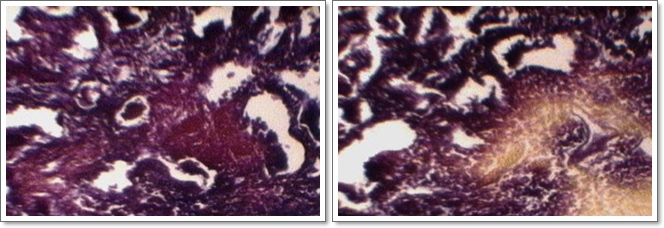

L'intestí prim:

L'intestí prim és un tub que en l'ésser humà té una llargària aproximada d'1,5 metres. Es troba arreplegat dins l'abdomen i es fixa a la paret posterior mitjançant una membrana conjuntiva molt resistent, anomenada mesenteri La mucosa forma uns plegaments en forma d'anell i està recoberta per petites vellositats molt juntes. Això augmenta la superfície útil de l'intestí, cosa que afavoreix l'absorció de les substàncies nutritives. La superfície interna està recoberta de glàndules productores de suc digestiu intestinal

L'intestí gruixut:

L'intestí gruixut té 3 segments: còlon ascendent, còlon transvers i còlon descendent. La mucosa, doblegada, té nombroses vellositats. En aquesta zona es troben poques glàndules. No té funció digestiva coneguda, i bàsicament es dedica a l'absorció d'aigua i algunes vitamines produ‹des per bacteris simbiòtics que hi viuen. La funció principal és l'emmagatzemament delsexcrements fins al moment de l'expulsió, regulada per l'acció d'un esfínter de contracció voluntària, anomenat anus. En l'home és capaç d'absorbir uns 6 litres d'aigua diaris.